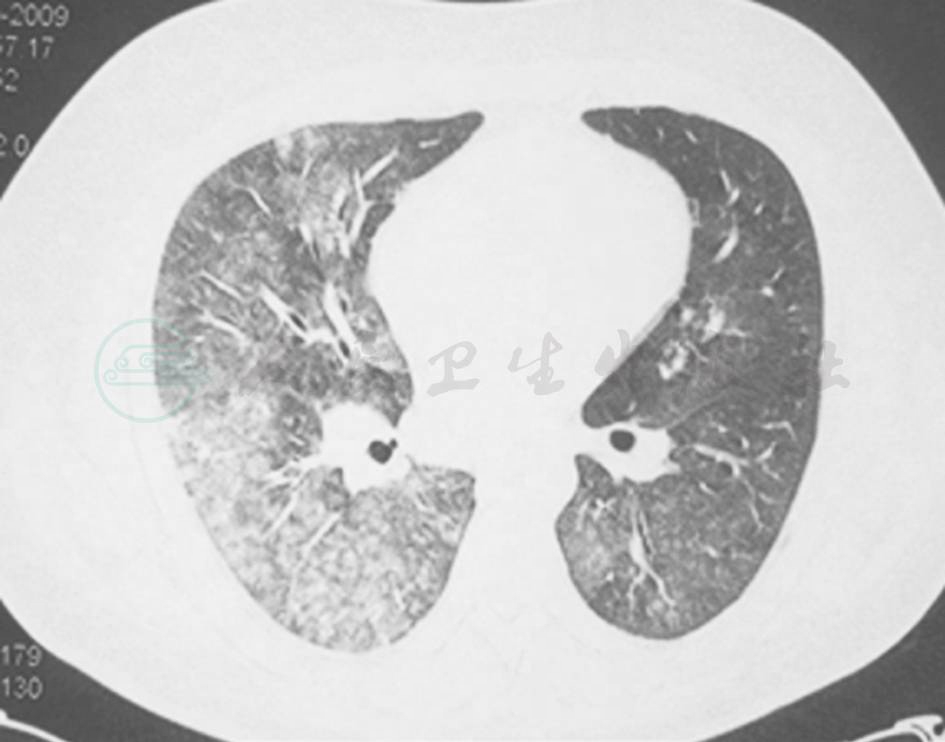

【影像学检查】

X线胸片:双侧肺多发斑片影,以右肺为著 (图1)。

图1 X线胸片

5.影像学检查显示双侧肺部多发斑片影,右侧为著。

本例患者在病程中表现为间断发热、咳嗽、咳痰,X线胸片显示肺部斑片状阴影,因此病变范围初步锁定在呼吸系统。此时,我们需要思考两个问题: